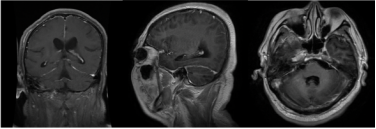

神清,胡言乱语,定向障碍,双耳听力明显下降,构音清晰;颅神经:双侧瞳孔直径4 mm,直接、间接对光反射迟钝,左眼相对性传入性瞳孔障碍(+)。

双下肢肌力0级,双下肢腱反射消失,双侧病理征(-);双上肢肌力4级以上,双上肢腱反射对称引出;T6水平以下针刺觉消失;双髋关节及以下音叉震动觉消失;颈软,颏胸距2指。

头颅MRA:椎动脉(R-VA)、基底动脉(BA)、右大脑中动脉(R-MCA)、右大脑后动脉(R-PCA)多发节段性重度狭窄(图4)。

患者定位诊断考虑胸段脊髓、大脑皮层、脑膜、视神经、听神经受累。定性诊断方面,患者整体病程分为两个阶段,第一阶段为脊髓病,第二阶段为中枢神经系统感染。

第一阶段病程:患者亚急性起病,病初为双下肢无力,3个月期间无明显变化,3个月后突然急性加重,不符合急性脊髓炎的病程特点,结合下胸段脊髓长节段长T2信号、水肿明显、脊髓可见可疑的血管流空影,需考虑脊髓血管病。进一步完善颈胸腰椎增强MRI,可见胸髓多发斑片状异常信号、脊膜不均匀增厚伴强化、脊髓周围多发迂曲血管影、脊髓表面含铁血黄素沉积(图6)。脊髓数字减影血管造影(DSA)可见左侧T10肋间动脉造影时早期静脉充盈、迂曲扩张,考虑为硬脊膜动静脉瘘(SDAVF)可能大(图7)。治疗方面,于神经外科行硬脊膜动静脉瘘切除术。

第二阶段病程:大剂量激素冲击治疗后出现发热、头痛、精神行为异常,腰穿脑脊液白细胞明显升高,考虑免疫抑制后继发感染性脑膜脑炎。脑脊液宏基因组学二代测序VZV序列数高,经抗病毒治疗后颅压、白细胞、蛋白及VZV序列数均明显下降,支持中枢神经系统VZV感染。此外,患者脑脊液蛋白显著升高,糖、氯化物降低,血结核感染特异性T细胞检测阳性,影像上脊膜增厚明显,需考虑合并中枢神经系统结核感染不除外。患者多发性脑梗死、局部蛛网膜下腔出血,颅内动脉多发节段性中重度狭窄,需考虑合并感染性血管炎可能。治疗方面,予以足量、足疗程抗病毒治疗及抗结核治疗。